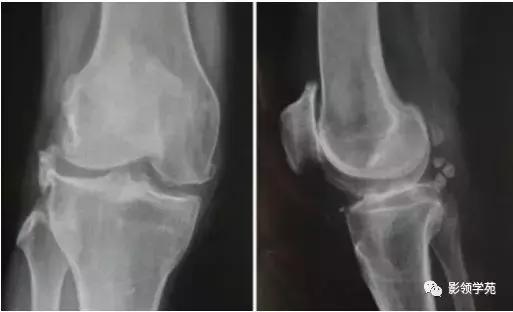

16、骨关节炎

- 常见(>50岁)

- 膝关节痛

- 早期:活动开始时痛、剧院征、上下楼梯时痛、下蹲起立时痛,休息能缓解;

- 中后期:负重痛、行走痛、夜间痛

- 短时晨僵 (<>

- 可有滑膜炎急性发作,关节间隙压痛,活动度减少

- 关节摩擦音,轻~中度关节积液

- X线摄片:负重位前后位、侧位和髌股关节切线位。